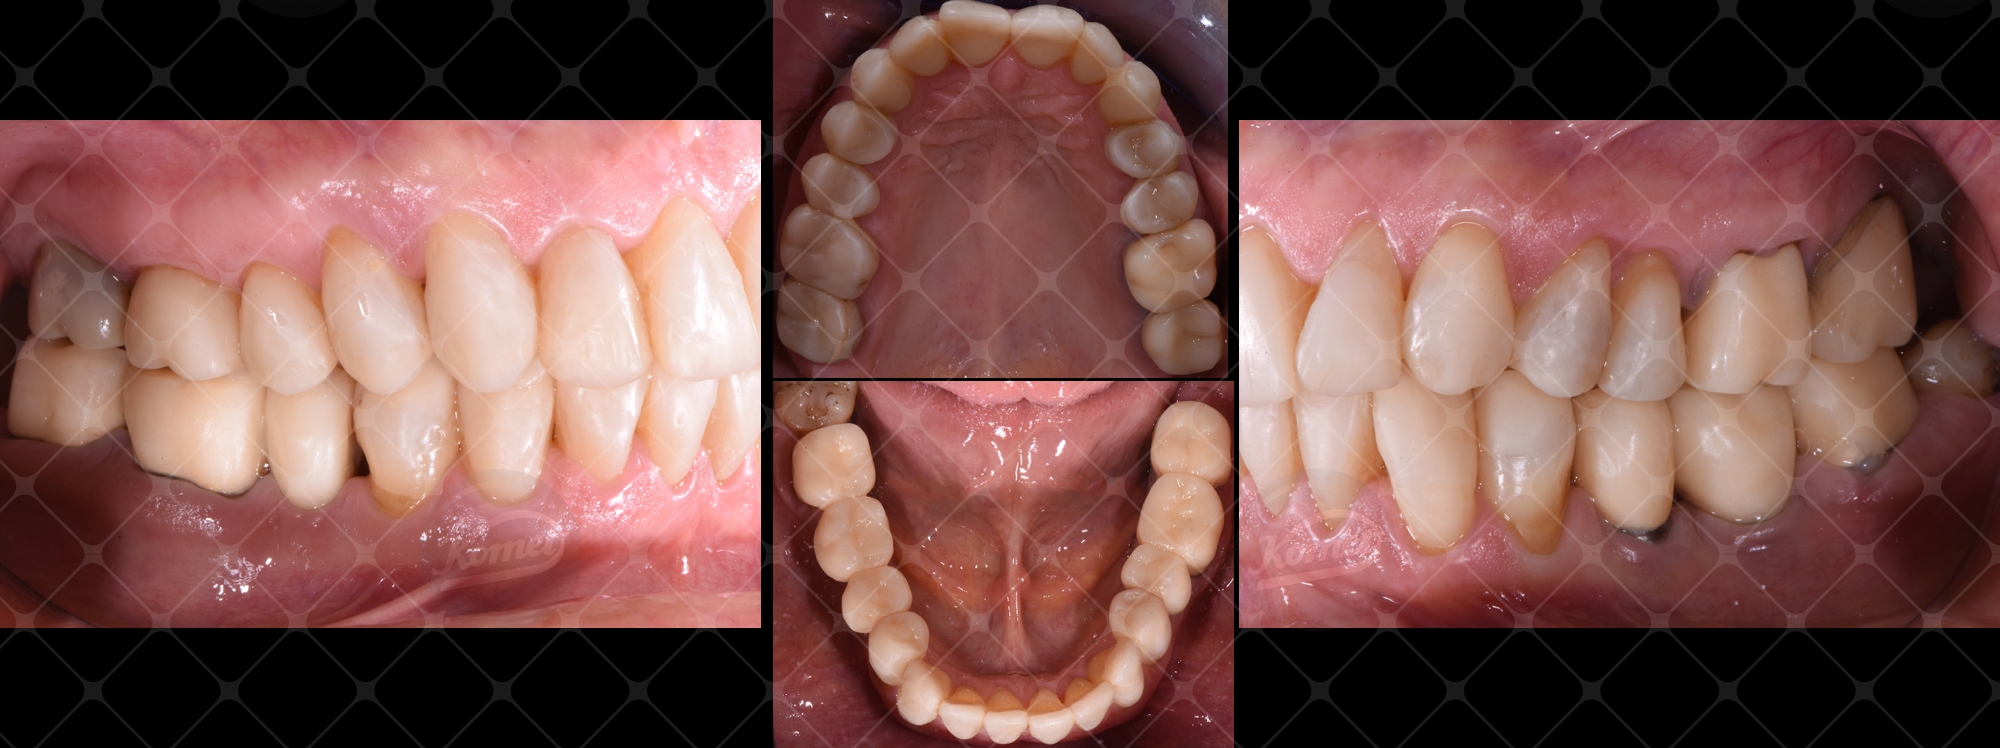

Fig. 16 Arcate riabilitate provvisoriamente in visione occlusale e laterale.

Fig. 16 Occlusal and lateral view of the temporarily rehabilitated arches.